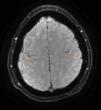

Se trata de un paciente varón de 37 años, que comenzó con alteraciones de la marcha en 2010. En la exploración se evidenció hiperreflexia, espasticidad y torpeza en las piernas, sin afectación sensitiva. Se realizó una analítica (incluyendo estudio de autoinmunidad y componente monoclonal) y una punción lumbar que fueron normales. El estudio neurofisiológico descartó la presencia de afectación de segunda motoneurona, mientras que la RM cerebral mostró hiperintensidad de los tractos corticoespinales en secuencia FLAIR y un ribete hipointenso en la circunvolución precentral en la secuencia SWI (fig. 1). En función de estos hallazgos se estableció el diagnóstico de sospecha de ELP y se inició tratamiento con riluzol. Con la evolución apareció piramidalismo en extremidades superiores y disartria espástica. Un segundo electromiograma descartó la afectación de segunda motoneurona 4 años tras el inicio de los síntomas, por lo que se estableció el diagnóstico definitivo de ELP1. La espasticidad se trató inicialmente con tetrazepam, con reducción de la misma, pero asociando debilidad generalizada que imposibilitaba la bipedestación. En septiembre de 2012 presentaba una marcha espástica de corto recorrido, precisando 2 bastones para marcha por interiores, con caídas frecuentes y silla de ruedas para marcha por exteriores. Presentaba también torpeza de la mano derecha, con caída de objetos. Su ALS Functional Rating Scale (ALSFRS-R) era de 32 (tabla 1). El balance motor (BM) era de 3-4/5 globalmente. Los reflejos osteotendinosos estaban exaltados en miembros inferiores, con clonus inagotable y reflejos cutáneo-plantares extensores. Presentaba espasticidad (Ashworth 2) que aumentaba al iniciar la marcha, con sensación de bloqueo. No se pudo realizar el test de la marcha, porque el paciente no era capaz de caminar 10m.